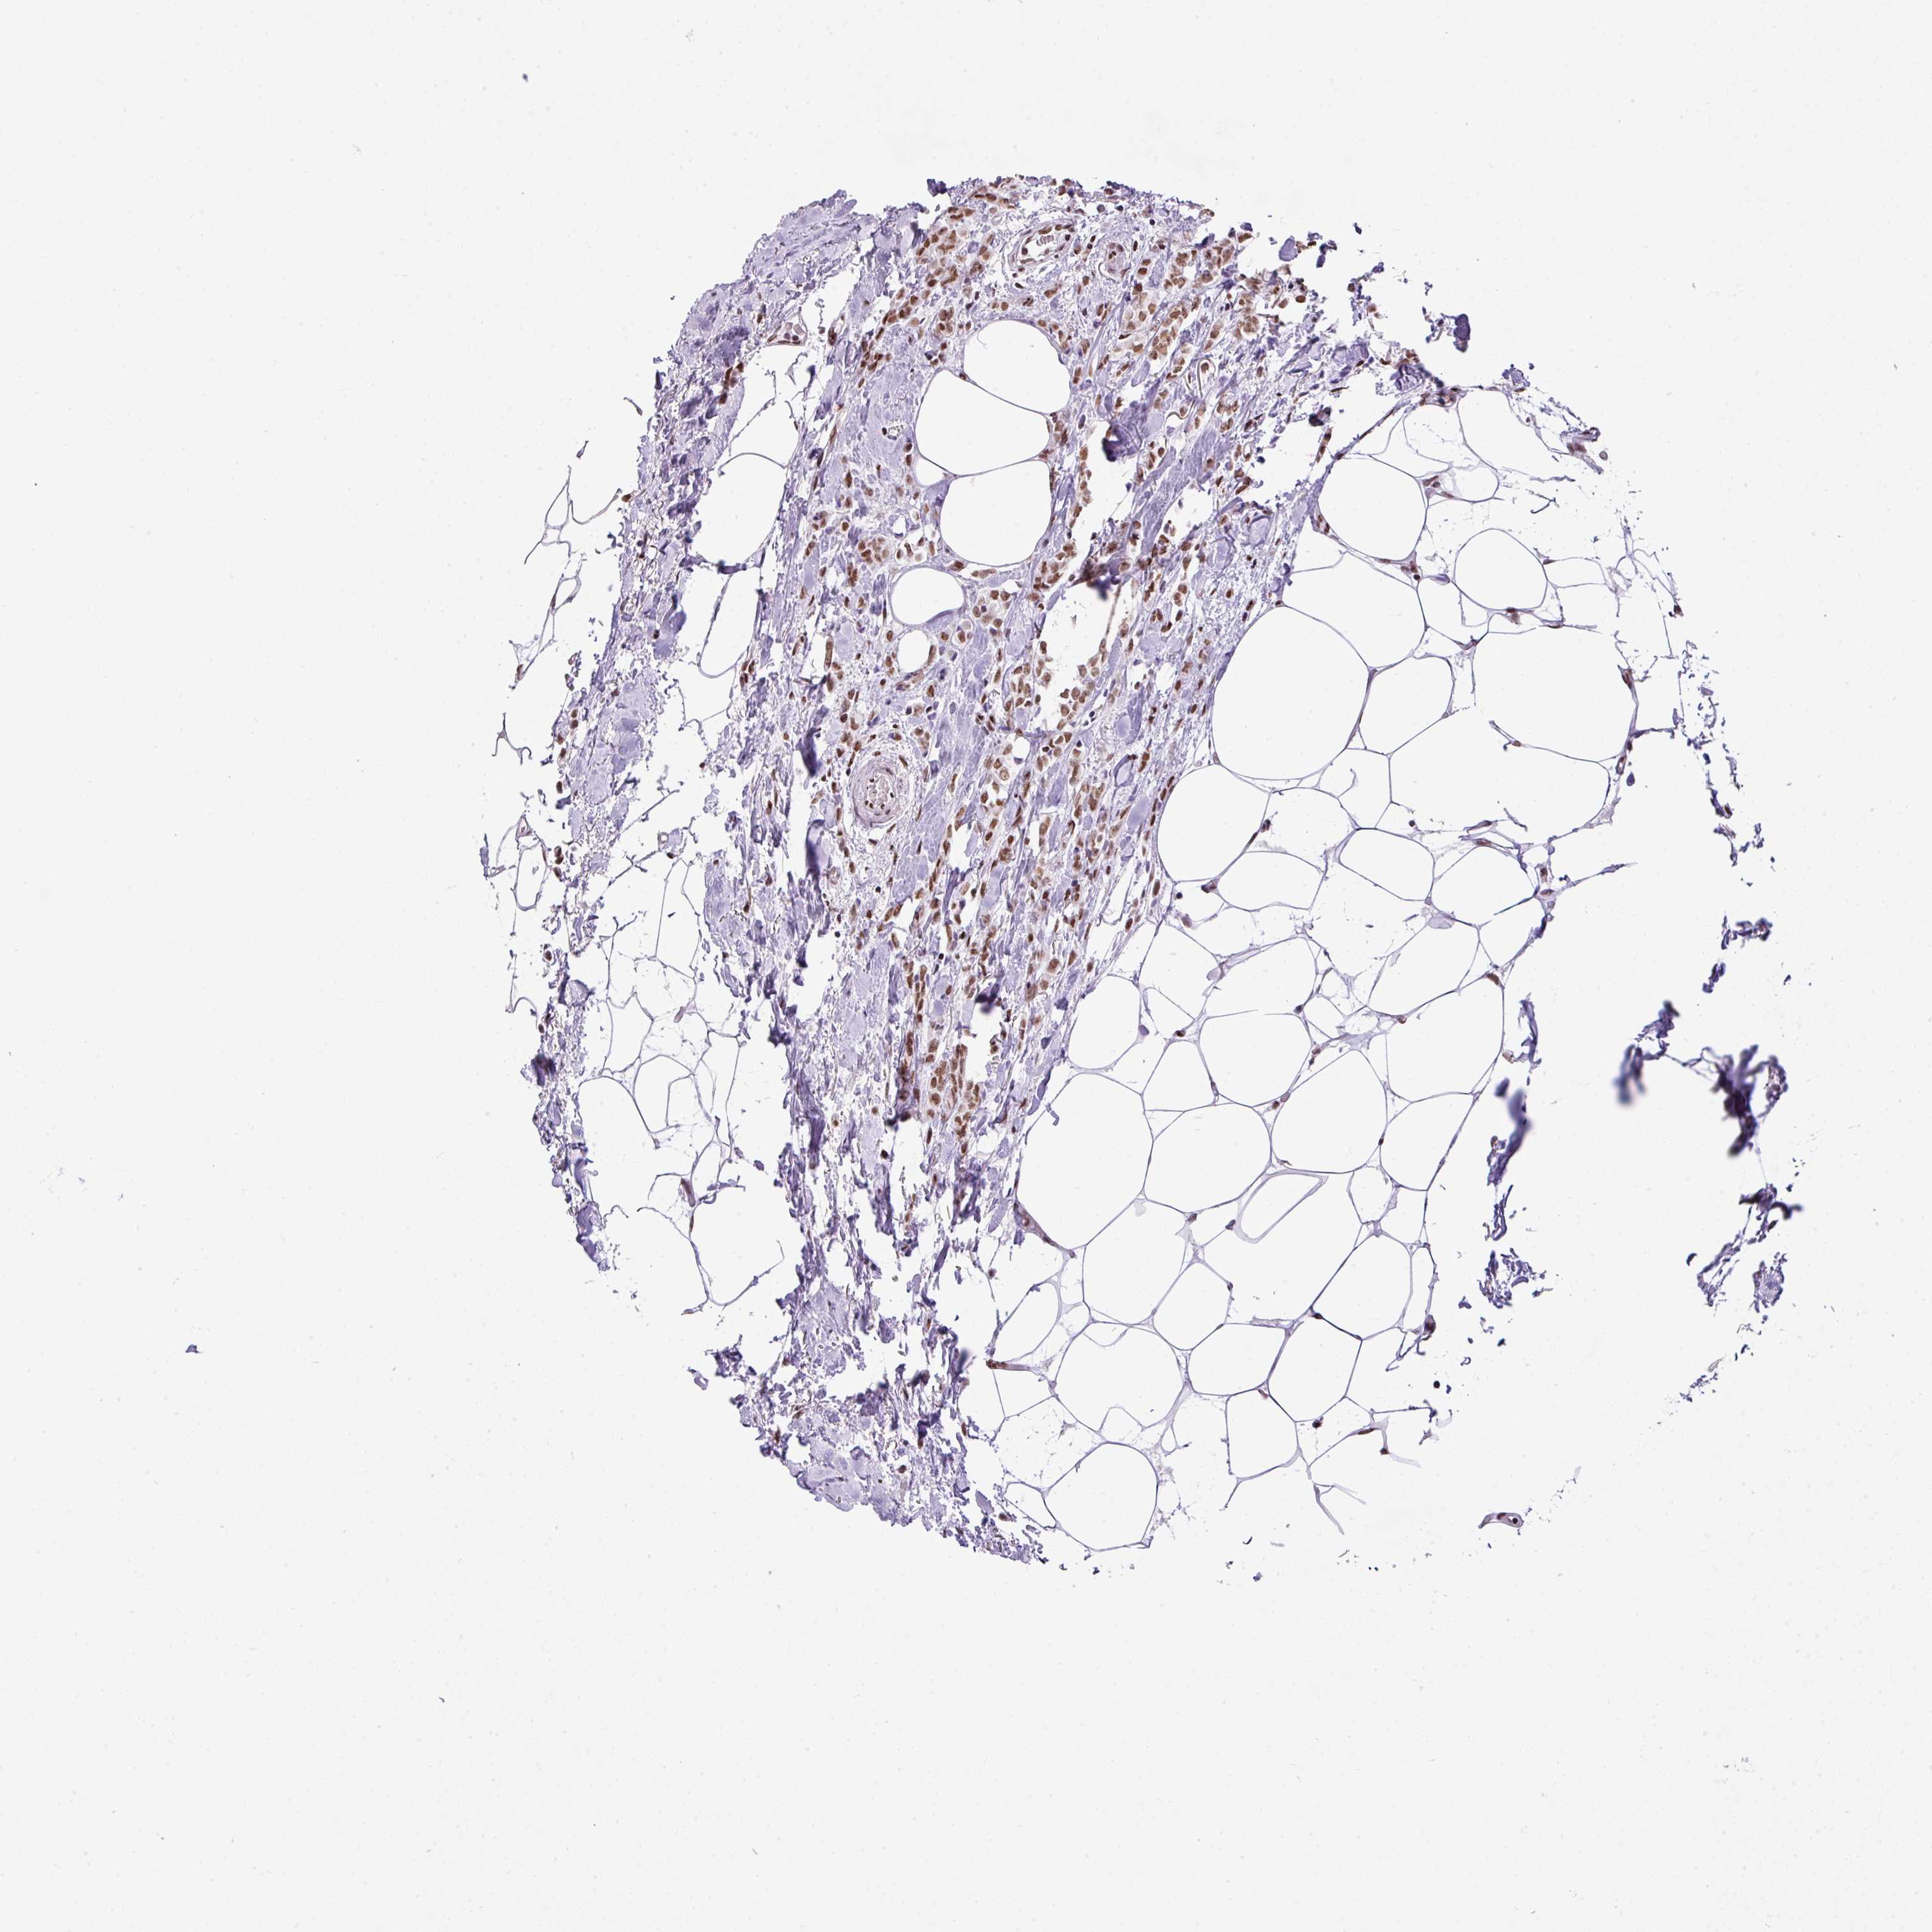

BRCA TCGA BRCA VALIDATION PROTEIN EXPRESSION

ANTIBODIES

AND

VALIDATION